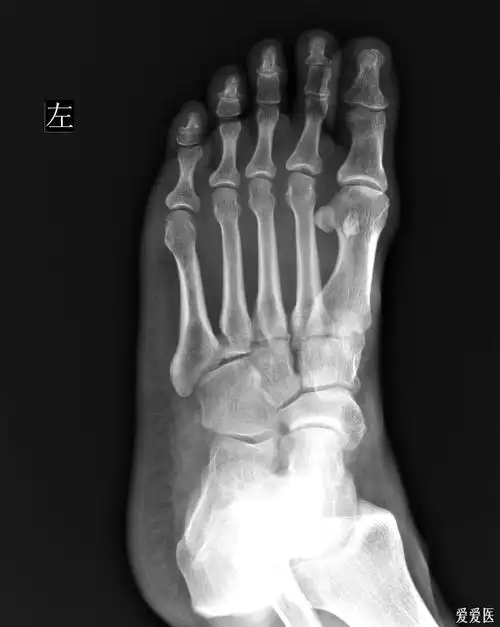

左足第五跖骨